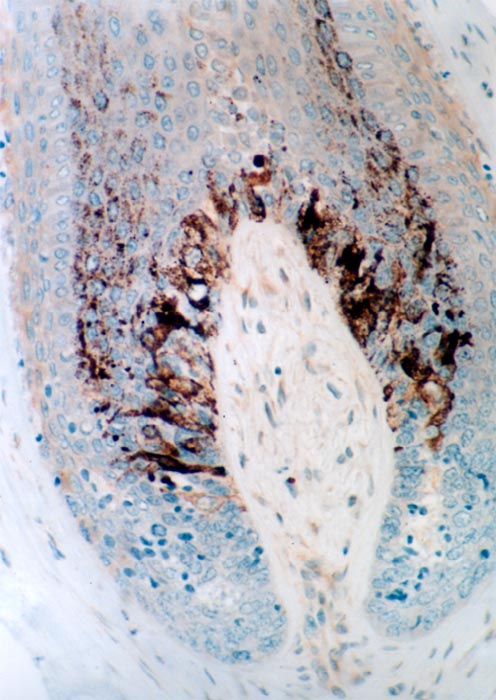

Evaluation of the melanic pigmentation of the hair bulb :

- Analysis of the transfer of melanocytes’ specks of melanin to the bulbous cells of the hair bulb

- Fontana coloration (quantitative scores)